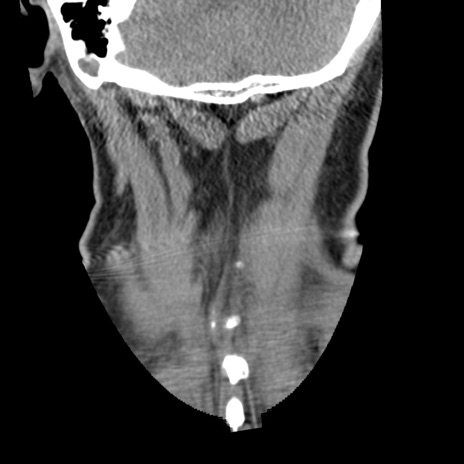

症例50 頚椎CT(冠状断像)

頚椎CT

矢状断像